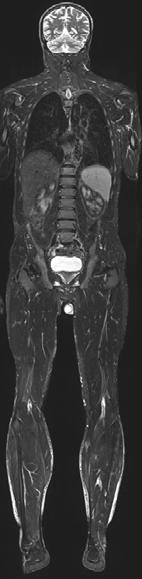

GanzkörperMR-Bildgebung mit koronarer Schnittbildebene. Die Erfassung der kompletten Körperlänge mit adäquater Weich teilauflösung ist ohne Einsatz ionisierender Strahlung möglich. Diese Technik wird in der onkologi schen, orthopä dischen und in der pädiatrischen Radiologie einge setzt.